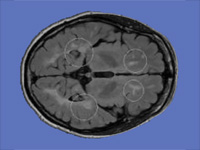

Generation of Connectivity-Preserving Surface Models of Multiple Sclerosis Lesions

In this article we introduce a software tool to build 3D surface models of Multiple Sclerosis (MS) brain lesions from 2D image stacks typically obtained through Magnetic Resonance Imaging (MRI). This tool allows users to create 3D models of MS lesions quickly and visualize the lesions and brain tissue using various visual attributes and configurations.

A Novel MRI Visualization Tool for White Matter Pathology in Multiple Sclerosis

We developed a tool to visualize MS lesions and their 3D surface models to show changes in the lesions over time. These can be shown as an animation to elucidate differences across scanning sessions. With this software, a volumetric sub-region can be selected from the 3D model for zooming or animation, and a point on the 3D model can be selected to highlight all lesions connected to it. The total volume of lesions can be calculated, displayed as a chart, and exported.

Concurrent Visualization of and Mapping between 2D and 3D Medical Images for Disease Pattern Analysis

We present a software tool to highlight and display regions of interest in 2D medical images and their 3D mesh model counterparts. This tool can help researchers visualize and compare brain lesions and tissues in 2D and 3D at the same time.